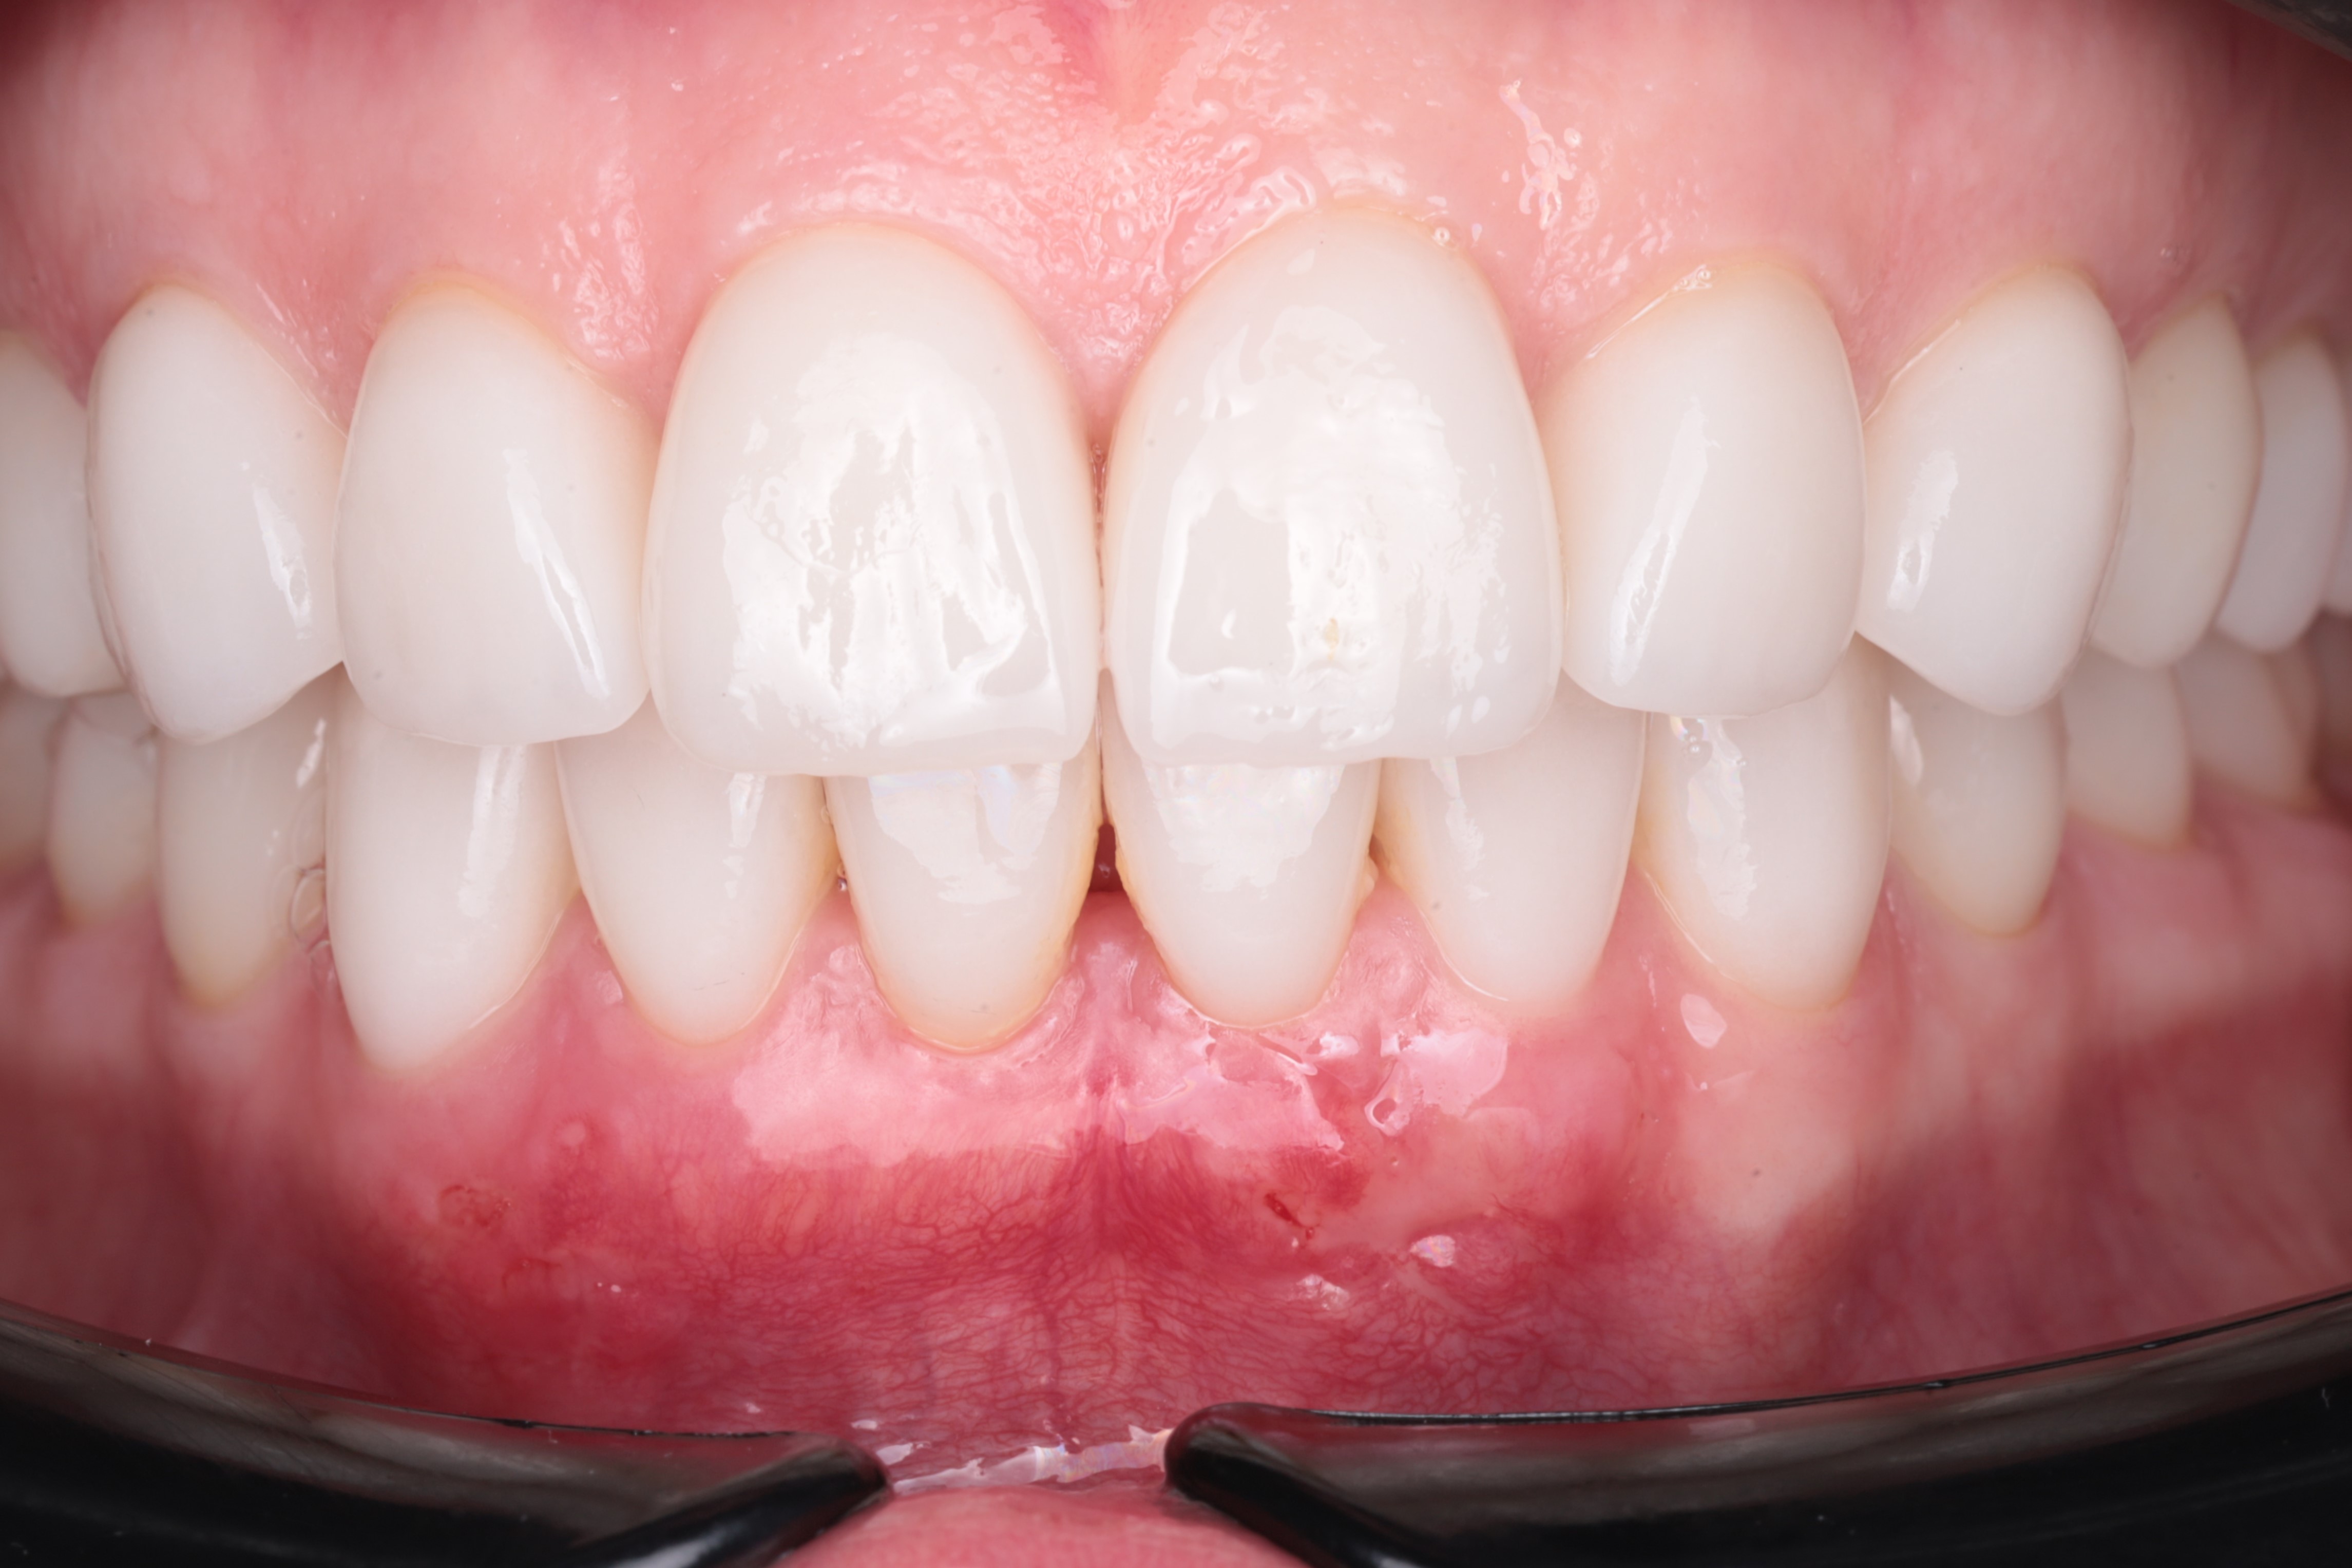

Исходная клиническая картина. Видим рецессии десны на зубах 4.2,4.1,3.1. Неудовлетворительную гигиену и хорошее прилегание ортопедической конструкции.